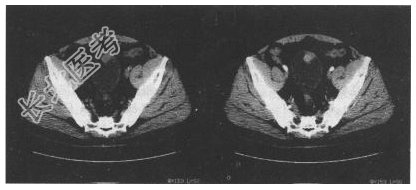

- [材料题] 患者,男,65岁。间断性血尿2个月,伴尿频、尿急1周,超声见膀胱内菜花状强回声影,尿常规红细胞(++),白细胞(+),查体未见明显异常。

- 简答题1、CT检查如下图,拟诊断为?